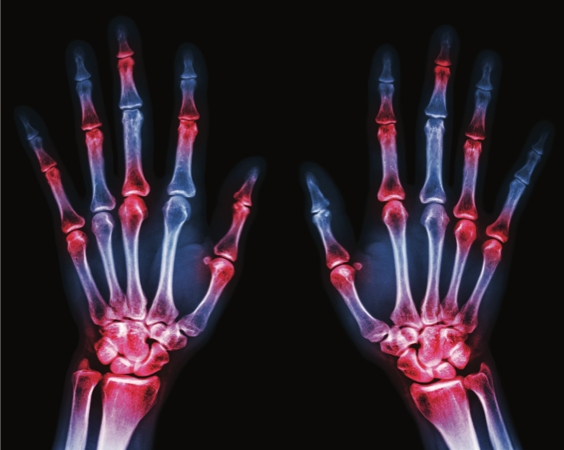

Rheumatoid arthritis (RA) is a chronic, systemic autoimmune disease that affects an estimated 1.5 million patients in the United States,1 making it the most common autoimmune inflammatory arthritis in adults. It is characterized by inflammation of the synovial membranes and leads to progressive erosion and destruction of cartilage and bone tissue in the affected joints.